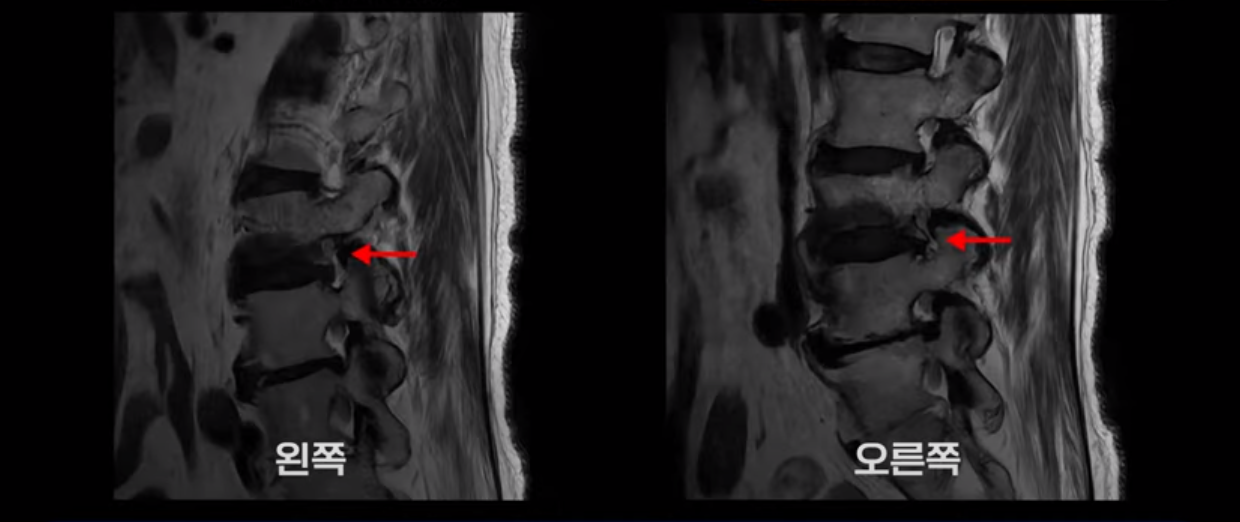

MRI를 보면 허리 4마디가 심하게 퇴행되어 있고

3번 뼈는 넘어질 때 생긴 압박골절이 있습니다.

3번 4번에는 척추관협착과 디스크 탈출이 보이고

4번 5번에는 척추관협착과 심한 디스크 파열이 있습니다.

5번 1번에는 뼈가 자라난 골극이 있고

기립근의 지방화도 심합니다. 또 3번 4번 마디에서는 신경가지가 빠져나가는 추간공이 왼쪽, 오른쪽 모두 많이 좁아져 있습니다.

이런 이유로 이 환자분은 왼쪽 다리는 마비가 생겨 힘이 빠지고 오른쪽 다리에는 심한 방사통이 있어서 휠체어까지 타야 하는 상태가 되었습니다. 이렇게 심하니까 대학병원에서 여러 마디 나사를 박는 유합술을 권유 받으셨는데요.